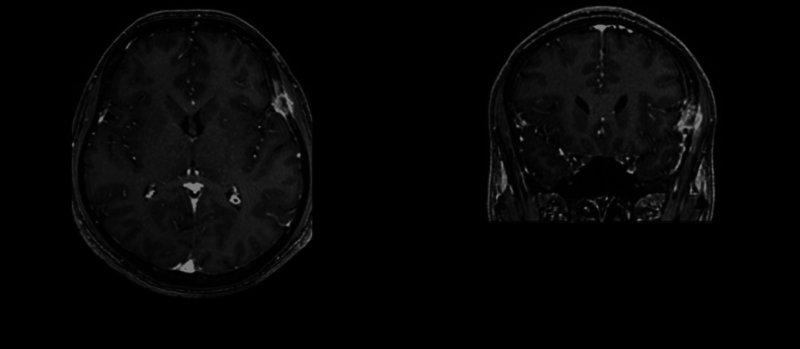

Introduction  Langerhans cell histiocytosis (LCH) is a rare proliferative systemic disease characterized by the growth of abnormal dendritic cells and wide-ranging organ involvement. This condition can affect individuals of all ages, but most commonly children, with a peak incidence in toddlers. Symptoms may vary depending on the affected organ or system. Case Report  A 43-year-old man presented with a left temporal stabbing headache unresponsive to management with therapy and nonsteroidal anti-inflammatory drugs. Initial evaluation revealed a contrast-enhanced left temporal extra-axial lesion with bone and muscle compromise. Differential diagnoses, including multiple myeloma, were explored. Initial laboratory tests and imaging studies showed no other abnormalities, except for splenomegaly and a residual granuloma in the left lung. En bloc resection of the lesion was recommended. The patient underwent surgical intervention, which included resection of the dural lesion and all borders of an infiltrating tumor within the temporalis muscle and the affected portion of the left temporal bone. Posterior pathological examination revealed LCH. Postoperative course was uneventful. Follow-up appointments were scheduled after pathology results confirmed the diagnosis. Patient has continued follow-up for the following 3 months after the surgical procedure. Further evaluations are pending. Discussion  This case report corresponds to a patient with LCH. These patients are individualized and stratified based on local or systemic involvement to determine the most appropriate type of management. This is a rare case as LCH is rare in older patients and the initial presented lesion initially mimicked a meningioma; however, its atypical behavior and associated lytic compromise led to consideration of possible differential diagnoses. Conclusion  LCH can present with lytic bone lesions, mimicking other conditions, including infiltrative neoplastic lesions. Early diagnosis and appropriate surgical management are essential for optimal patient outcomes. Long-term follow-up is crucial to monitor disease progression and response to treatment.

Abstract Image